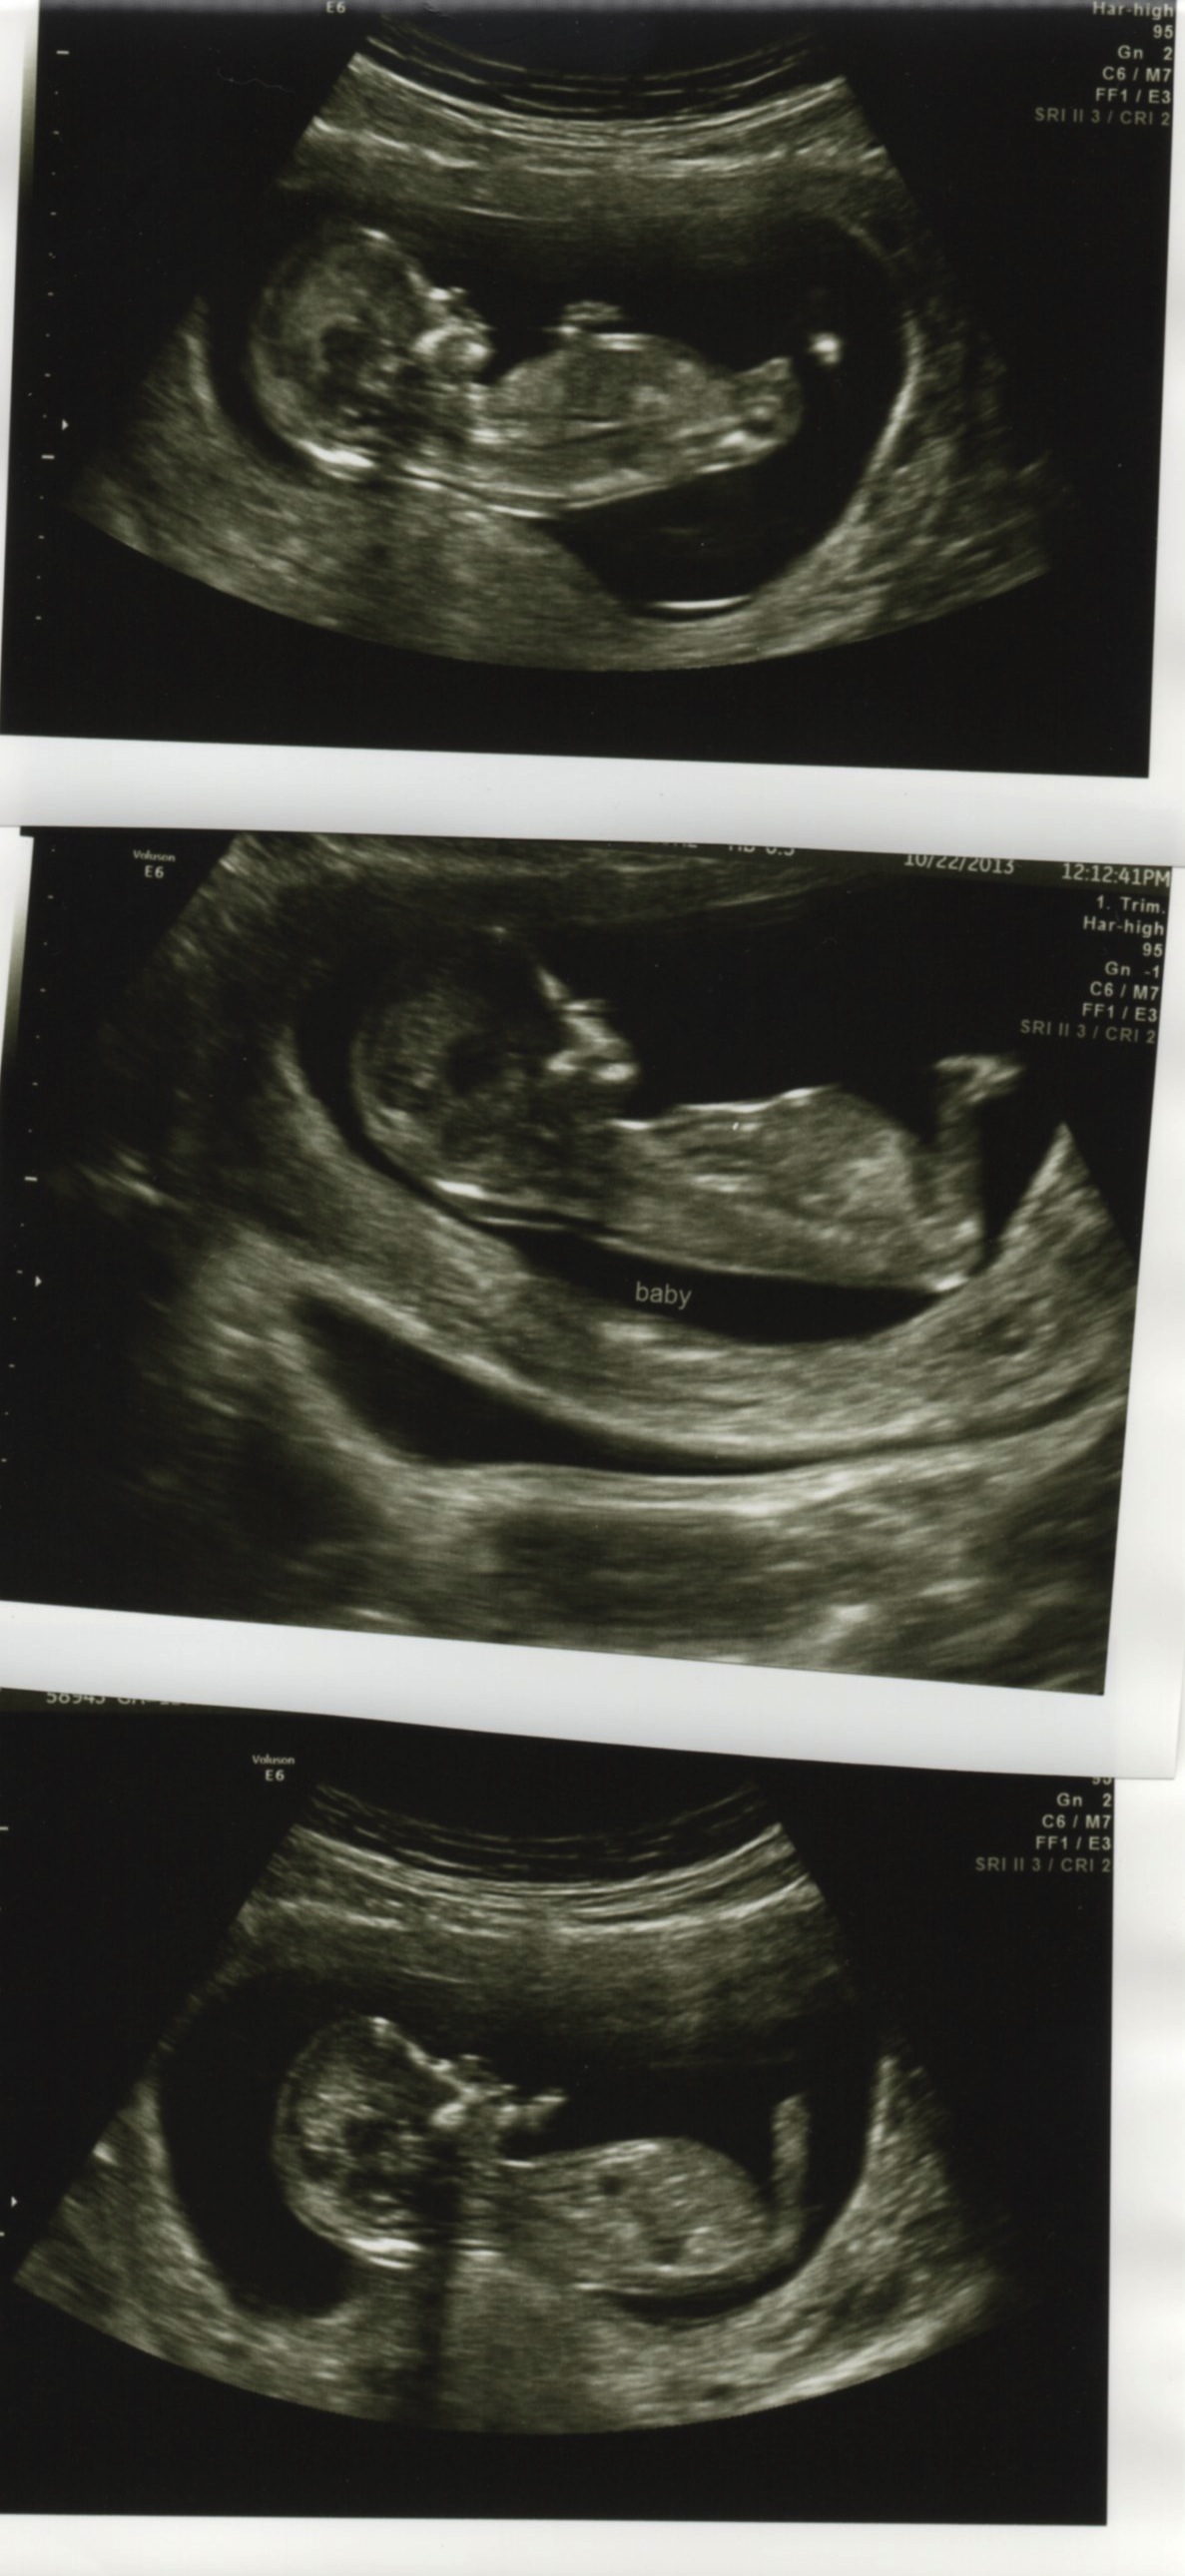

Hopefully these scanned clear enough that you can see.I'm new here (and SO happy there are other people who know this theory, my friends think I'm nuts!).

Boy or girl...whatcha think?

Nub guesses needed! 12w2d US (several profile shots)

1st pic looks girly. 2nd & 3rd are a bit blurry maybe?

Yeah...the second one is blurry compared to viewing it in person. I'm not sure there's a nub there, or not.

girl lean. baby's back is stretched flat in the first picture, so it might throw it off a little bit.

Hmmm. I will lean a bit girl. Angle is girly still. But the shape is throwing me off. Could be a fork I am seeing, just not clearly. But could be a bobble, which would lean me boy. Sorry. I'll give a 60-40 girly lean.